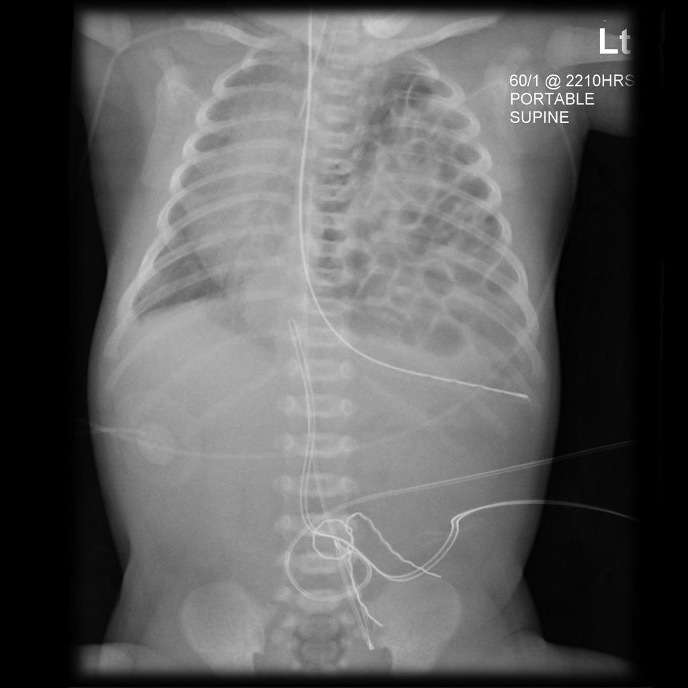

Diaphragmatic hernia

Misplaced NG